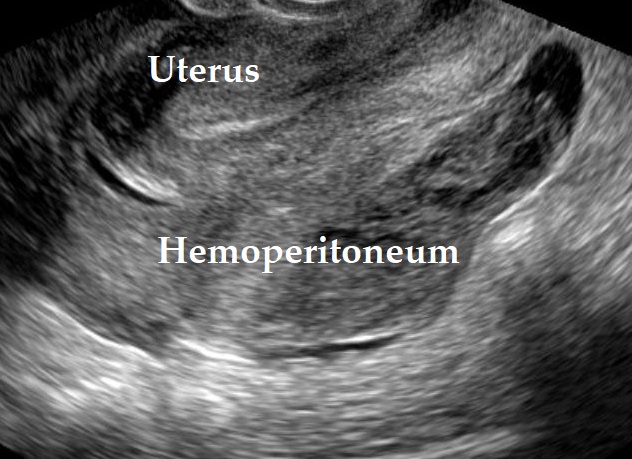

- Mucinous ascites may present after cyst rupture.

Pseudomyxoma peritonei – Typically has all of the following characteristics:

- Mucinous ascites

- Peritoneal implants

- Mucinous tumor of the appendix

Only rarely does a pseudomyxoma peritonei develop from a primary ovarian neoplasia (mature teratoma containing a mucinous neoplasm) (Carr, N. J., et al., 2016).